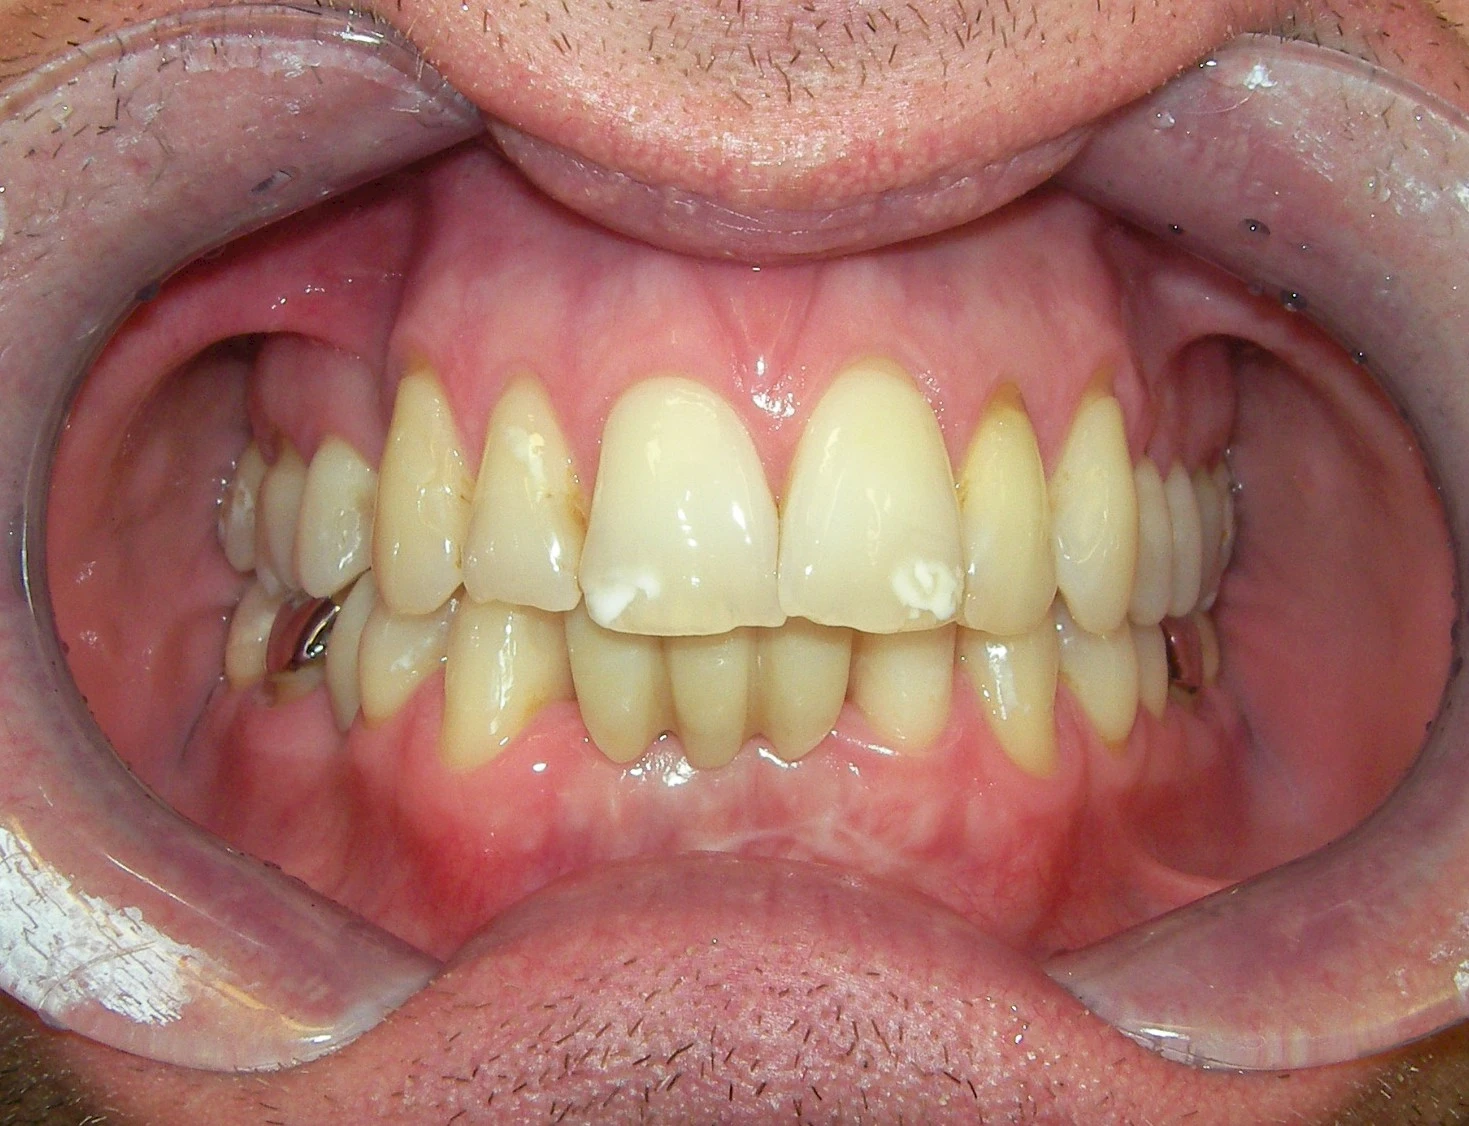

Verfärbungen an Zähnen können außen aufgelagert oder im Zahn eingelagert sein.

Von außen (exogen) eher dunkel gefärbt und meist mehrere Zähne betroffen:

- Genußmittel (Tee, Kaffee, Rauchen)

- Medikamente (z. B. Eisen)

Äußere Verfärbungen durch Genußmittel oder Medikamente (Eisen!) lassen sich meist nur durch den Zahnarzt z. B. mit einer professionellen Zahnreinigung entfernen.